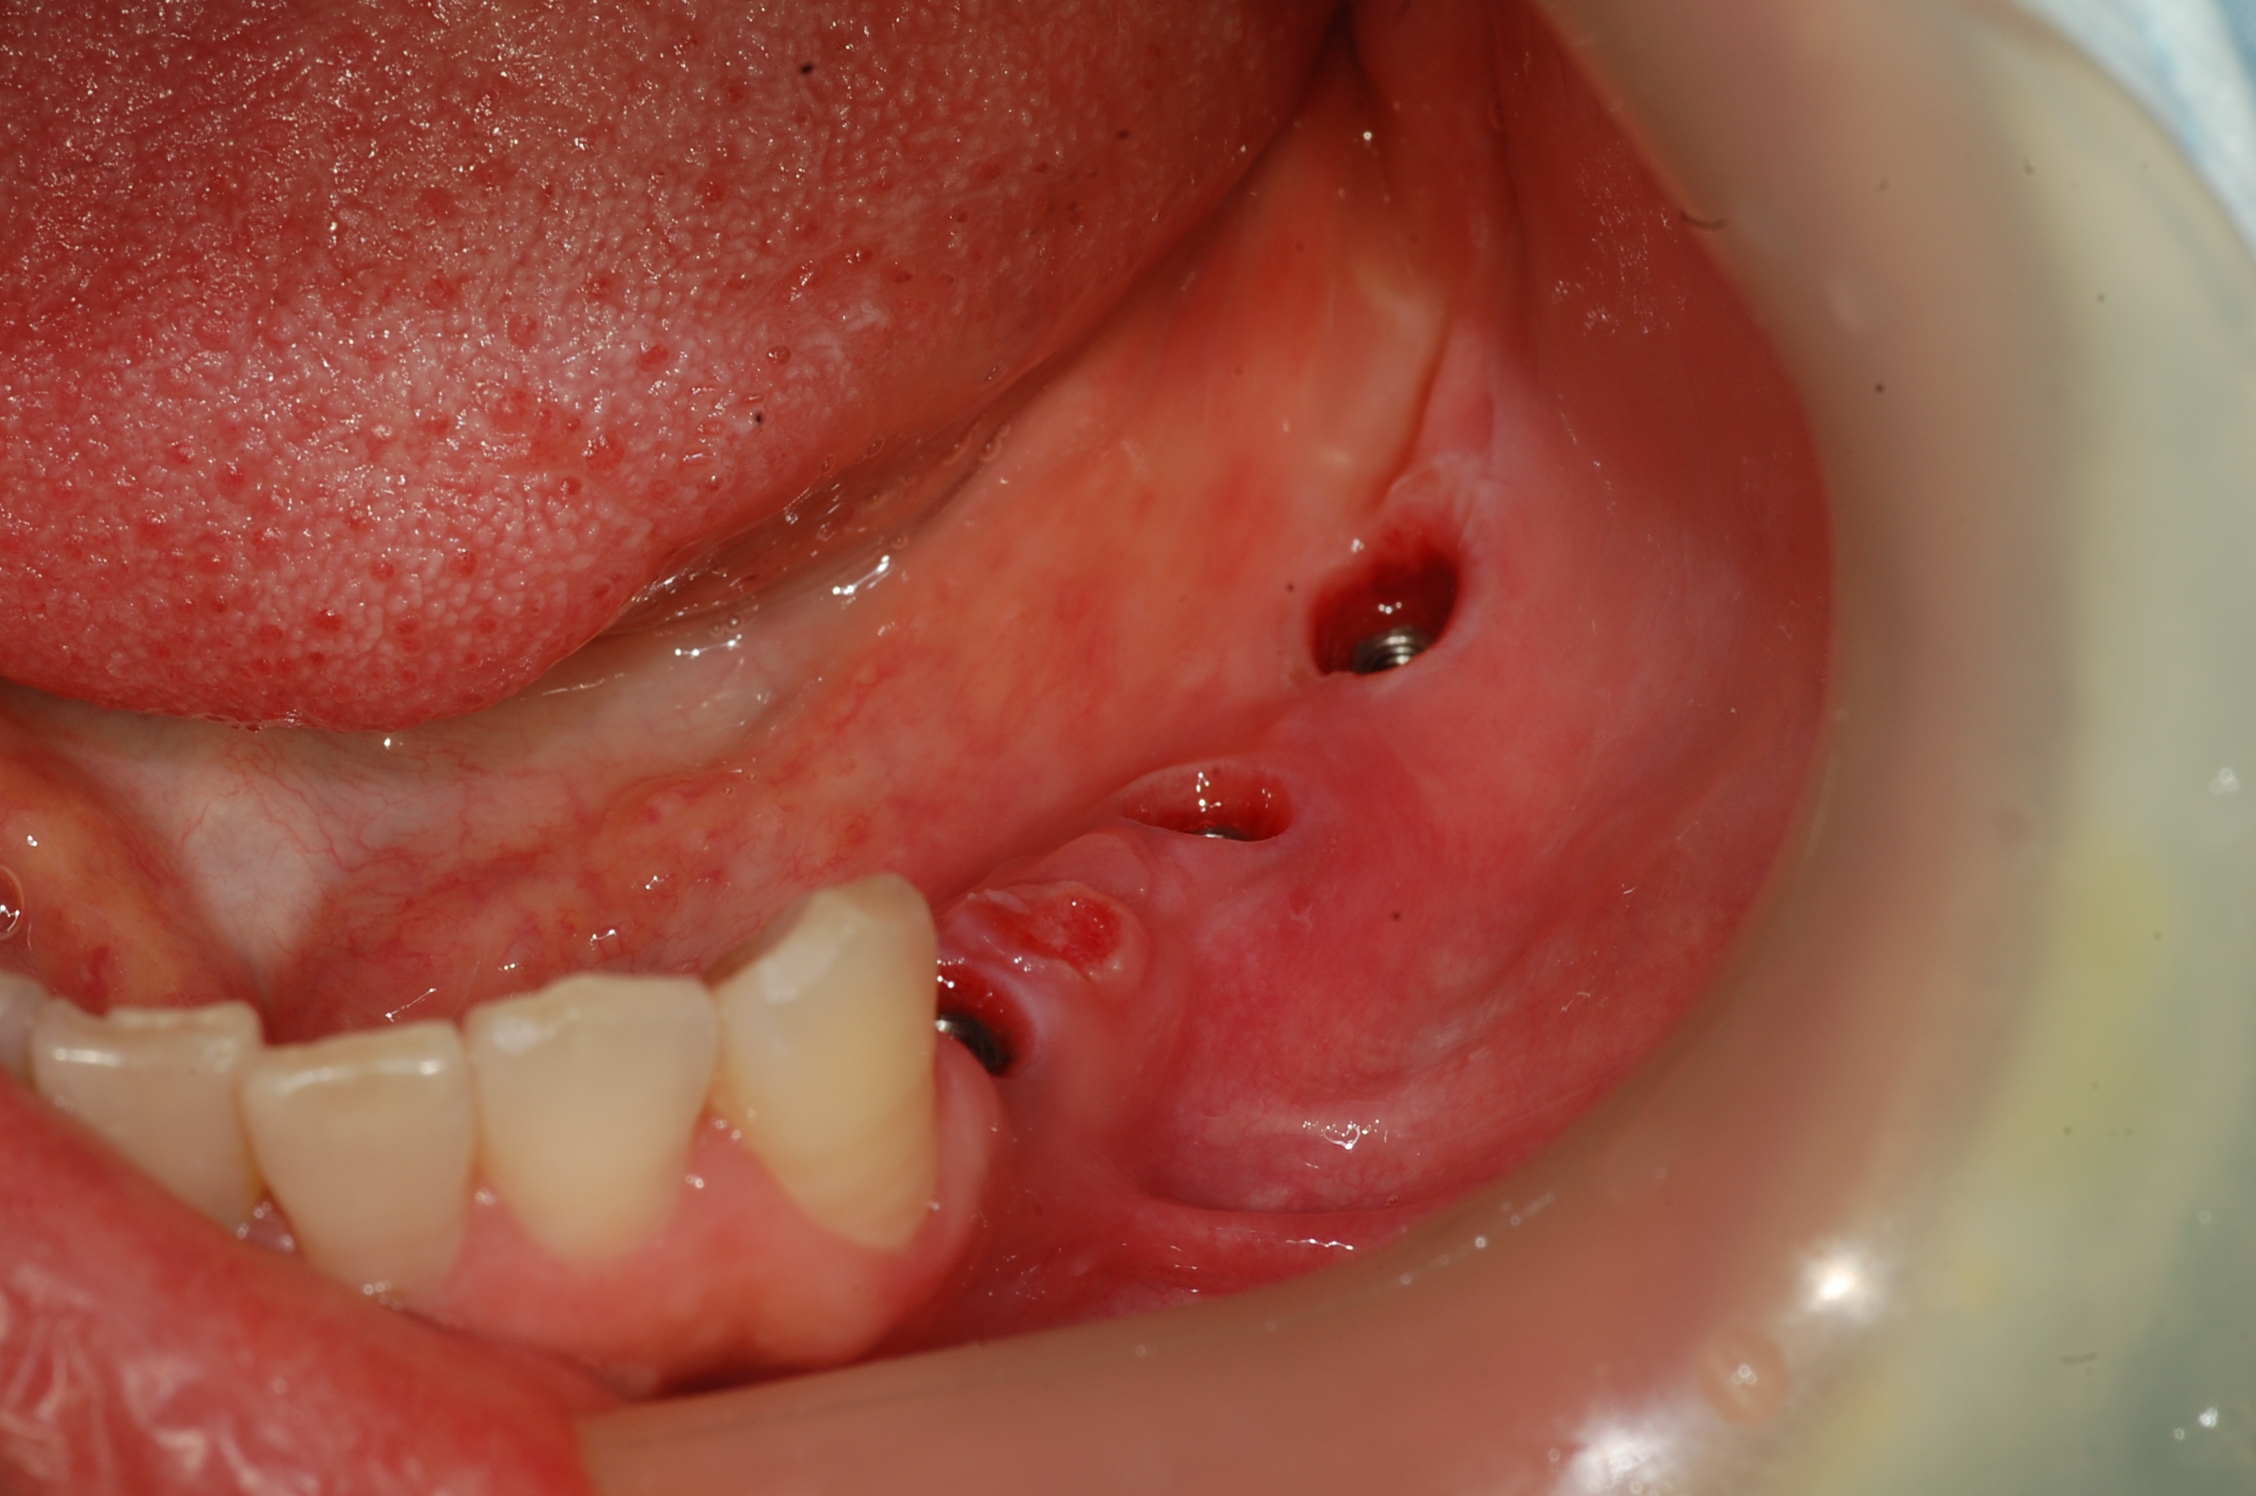

[임플란트] 제목 : 하악구치

임플란트 보철